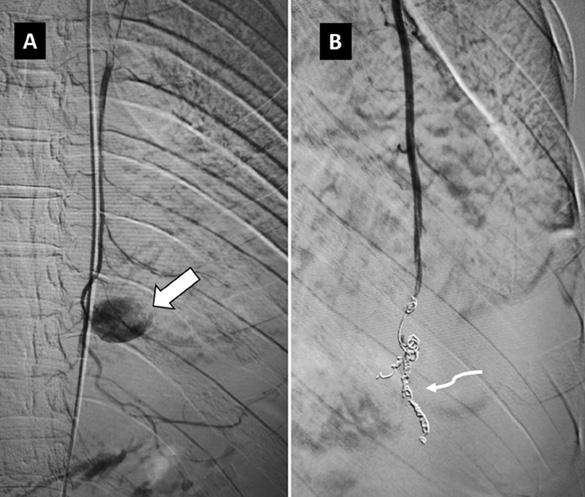

By using right common femoral arterial access, superselective cannulation of the left IMA was performed with a microcatheter (2.3F Progreat, Terumo Medical Corporation, New Jersey, USA). The initial angiogram confirmed the presence of a pseudoaneurysm originating from the distal IMA, without active contrast-extravasation. The pseudoaneurysm was embolized by using the ‘sandwich technique’ with two 5 mm x 14 cm and two 4 mm x 14 cm Nester microcoils (Cook Medical, Bloomington, USA). Post-embolization, there was non-visualisation of pseudoaneurysm (Figure 2). The total procedure time was approximately 22 minutes.